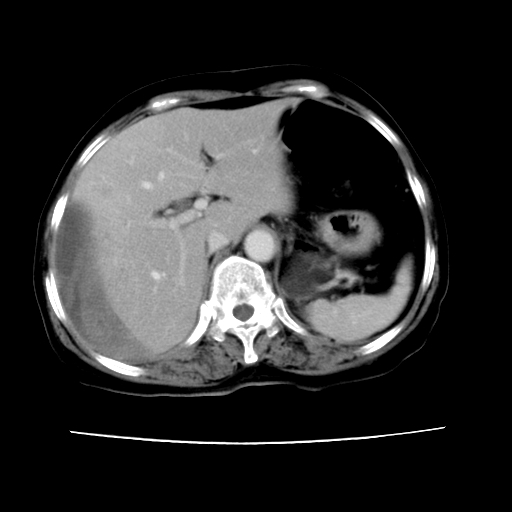

标题: CT16642:男62岁,突发性上腹部疼痛来诊。请讨论!

2008-6-10ct平扫

ct增强

6月份ct片显示肝内巨大混杂密度团块,伴包膜下积液(内含液液平面),增强多无明显强化。只能考虑肝占位病变,并肝内、血膜下血肿。肝ca并出血多见,而肝血管瘤并破裂出血少见。

6月份ct片显示肝内巨大混杂密度团块,伴包膜下积液(内含液液平面),增强多无明显强化。只能考虑肝占位病变,并肝内、包膜下血肿。肝ca并出血多见,而肝血管瘤并破裂出血少见。